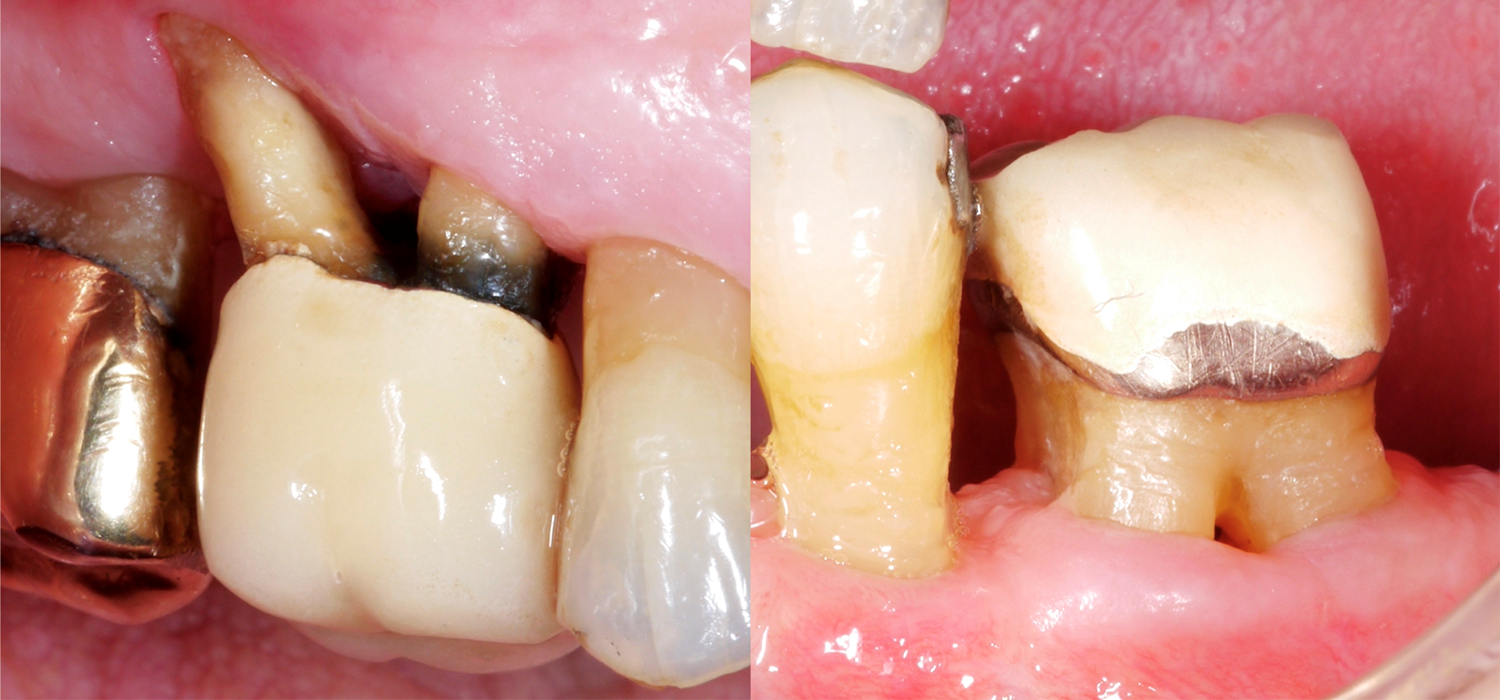

Разбира се, при зъбите с многобройни корени лечението често е много по-трудно, особено ако са засегнати от фуркации. Защо областта на фуркацията е толкова предизвикателна? В сравнение със зъбите с един корен достъпът за механично почистване на кореновата повърхност е много по-труден, входът на фуркацията често може да бъде много малък/тесен, а може да има и допълнителни анатомични особености, като например емайлови издатини.

В наскоро публикувано проучване от Франкфурт (Eickholz 2021) са разгледани специално зъби с открити фуркации. Те са изследвали общо 265 зъба с открита фуркация при 160 пациенти; всички пациенти са били подложени на поддържащо пародонтално лечение в продължение на най-малко пет години. Въз основа на тези данни трябва да вземем предвид следните важни моменти:

• Зъбите с фуркационен дефект III степен се губят по-често от зъбите с един корен например и след около 10 години поддържащо пародонтално лечение трябва да очакваме, че около една трета от тези зъби ще бъдат извадени. Същевременно обаче това означава, че две трети от тези силно увредени в пародонтално отношение зъби все още са на мястото си.

• Възможните причини за екстракция са много - от пародонтални проблеми до кариеси и/или протетични проблеми.

• Следните рискови фактори за загуба са идентифицирани за зъби с дефект на фуркацията: по-високо ниво на загуба на кост в началото на лечението и по-голяма дълбочина на сондиране в началото на поддържащото лечение.